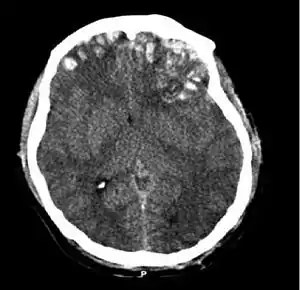

Movement disorders that may develop after TBI include tremor, ataxia (uncoordinated muscle movements), spasticity (muscle contractions are overactive), myoclonus (shock-like contractions of muscles), and loss of movement range and control (in particular with a loss of movement repertoire).[95][152] The risk of post-traumatic seizures increases with severity of trauma (image at right) and is particularly elevated with certain types of brain trauma such as cerebral contusions or hematomas.[142] People with early seizures, those occurring within a week of injury, have an increased risk of post-traumatic epilepsy (recurrent seizures occurring more than a week after the initial trauma).[153] People may lose or experience altered vision, hearing, or smell.[10]